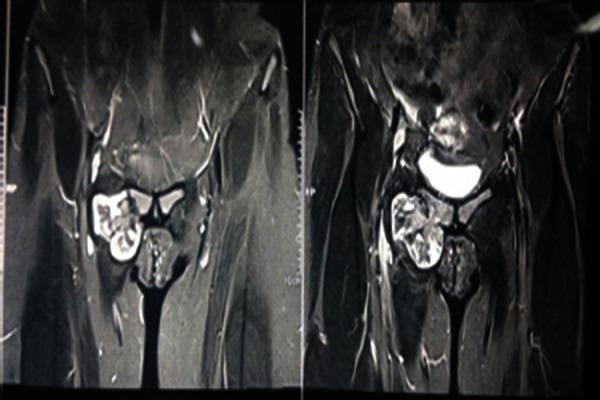

We present a case of 18 year female, who came with a swelling in right groin since 2 years which was diagnosed to be osteochondroma on x-ray and magnetic resonance imaging. Excision biopsy was done as the patient wanted it to be removed for cosmetic purpose and confirmed it to be non-malignant osteochondroma. There has been no recurrence even after 1 year of follow up.

我们报告一例18岁女性病例,该患者自两年前起右腹股沟出现肿胀,经X线和磁共振成像诊断为骨软骨瘤。由于患者出于美容目的希望切除,遂进行了切除活检,结果证实为非恶性骨软骨瘤。随访1年,未见复发。